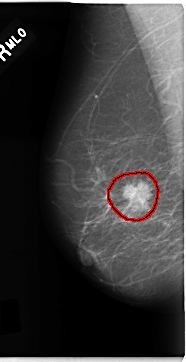

C_0181_1.RIGHT_MLO

RIGHT_MLO LINES 4704 PIXELS_PER_LINE 2408 BITS_PER_PIXEL 12 RESOLUTION 50 OVERLAY

FILE: C_0181_1.RIGHT_MLO.OVERLAY

TOTAL_ABNORMALITIES 1

ABNORMALITY 1

LESION_TYPE MASS SHAPE IRREGULAR MARGINS SPICULATED

ASSESSMENT 5

SUBTLETY 5

PATHOLOGY MALIGNANT

TOTAL_OUTLINES 1

BOUNDARY